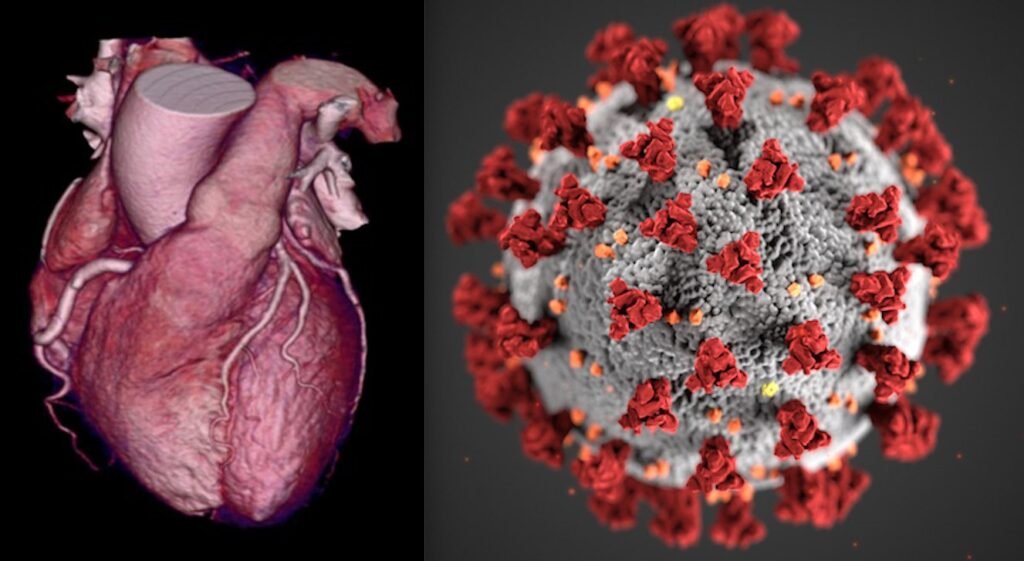

Heart Disease by Covid

Patients hospitalized with Covid-19 may develop heart failure even if they do not have a previous history of heart disease or cardiovascular risk factors, although the risk is low, according to a study published on Monday in the Journal of the American College of Cardiology.

Among 6,439 hospitalized Covid-19 patients, doctors found 37 patients (0.6%) with no history of heart failure who developed new cases during their hospitalization – including eight in their 40s, on average, who had no previous cardiovascular disease or risk factors.

It is not clear yet whether new-onset heart failure in these patients is an indirect effect of critical illness or a direct effect of the virus invading the heart, said study co-author Dr Anu Lala of the Icahn School of Medicine at Mount Sinai in New York, in a statement.

“Importantly,” she added, “though symptoms of heart failure – particularly shortness of breath – can mimic symptoms associated with Covid-19, being alerted to the findings of this study may prompt clinicians to monitor for signs of congestion more consistent with heart failure than Covid-19 alone.”